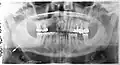

- Контроль этапов лечения и динамики течения заболеваний (качество пломбировки канала, штифты, имплантаты и пр.).